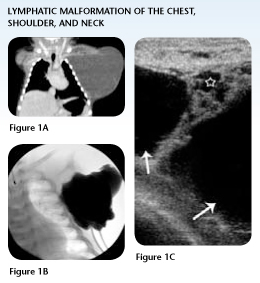

Case Study 1: Lymphatic Malformation of the Neck, Shoulder and Chest

In the first few hours of life, Hayden underwent a CT scan that clearly illustrated for the pediatric surgeon in Kentucky the extent of the mass, previously seen on a prenatal ultrasound.

The mass involved the left neck, shoulder and the entire length of the left chest wall. Surgical mapping indicated extensive surgical removal involving major nerves and vital structures, resulting in an up to 50 percent chance of recurrence.

After consultation with The Lymphatic Malformation Center at Nationwide Children's Hospital, the surgeon decided against operative removal and transferred Hayden to Nationwide Children's for definitive interventional radiological treatment.

Following the five-hour trip from southern Kentucky, Hayden, age 6 months, underwent his first two-hour procedure that ablated more than 95 percent of the lymphatic malfmormation, through a 2 mm opening in the skin.

Hayden came back six months later to complete his second procedure, which only took 60 minutes, and was released to go home with only a Spiderman bandaid for a dressing, and no remaining cysts for treatment.